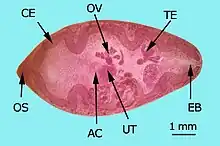

AC: acetabulum (ventral sucker)

CE: cecum, EB: excretory bladder

OS: oral sucker, OV: ovary

TE: testes, UT: uterus

Species of Paragonimus vary in size; the adult stage might attain a length of up to 15 millimetres (0.59 in) and a width of up to 8 mm (0.31 in).[5] The adult flatworm has an oval shape body with spines covering its thick tegument. Both the oral sucker and acetabulum are round and muscular. The acetabulum is slightly bigger than the oral sucker – 0.19 mm and 0.12 mm, respectively.[5] Ovaries are located behind the acetabulum and posterior to the ovary are the testes. The seminal receptacle, the uterus and its metraterm, the thick-walled terminal part, lie between the acetabulum and the ovary.[5]